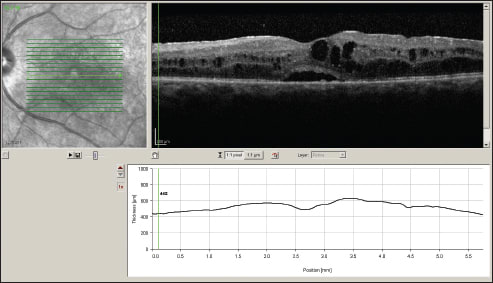

On examination, best-corrected visual acuity was 20/200 OU. Dilated fundus exam revealed 1+ cells in the anterior vitreous of both eyes, early PSC cataract and florid CME in both eyes. In addition, both eyes showed arteriolar attenuation and subtle non-pigmented chorioretinal lesions. Her work up was significant for a positive HLA-A29 haplotype, and OCT confirmed CME in both eyes (Figure 1).

Figure 1. OCT scans of the left eye (top image) and the right eye (bottom image) at time of presentation.